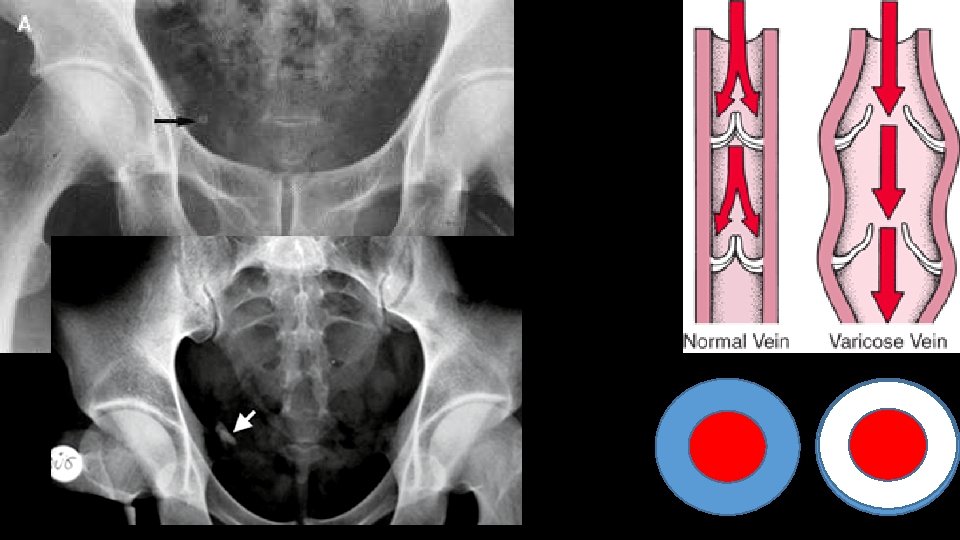

Urolithiasis Calculi along urinary tract • Anywhere • Kidney • Ureter • Bladder

Mimics